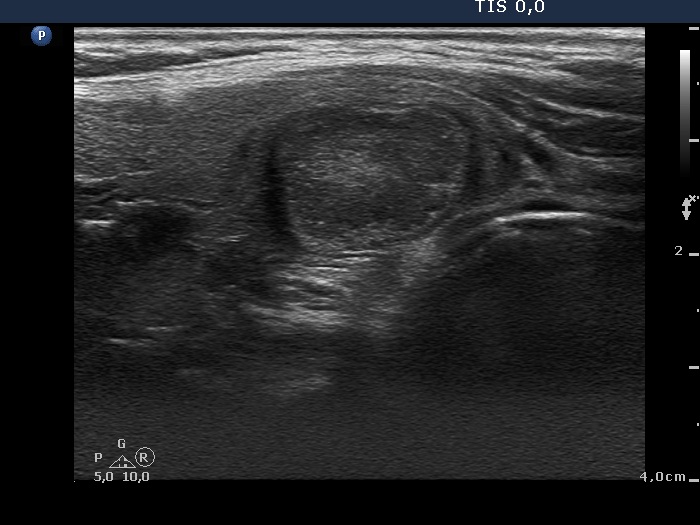

Ultrasonography. There were multiple nodules with different echogenicity next to each other in the lower two third of the right lobe. The discrete lesions presented a type perinodular vascularity. The left lobe was intact.

Cytology was performed from the hypoechogenic nodule. Cytological pattern corresponded to a follicular tumor without any atypia.